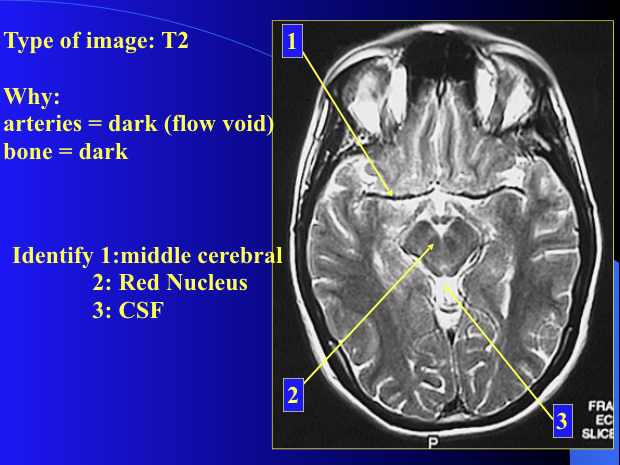

T2

What is Flow Void?

In which imaging can you see it and how does it look?

Flowing blood (not bleeding) appears dark on a T2 but not on CT/T1.